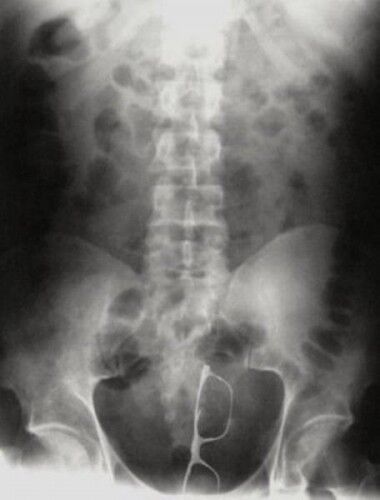

Röntgen Filminde İnsanların İçinden Çıkan Acayip Maddeler

3 / 9